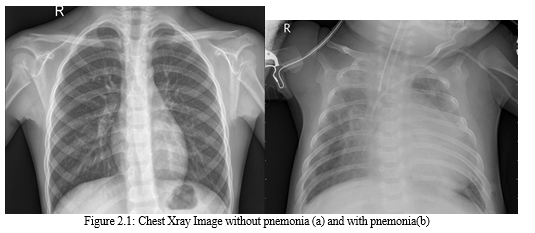

The details of number of images under each part is shown in Table I. Some sample chest X-ray images are given in Fig. 2.1.